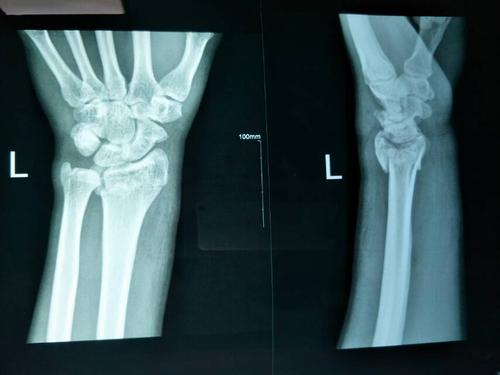

患者59岁,左桡骨远端骨折,骨折断端明显

左桡骨远端粉碎性骨折(复位前)

手法整复桡骨远端骨折

左桡骨远端粉碎性骨折